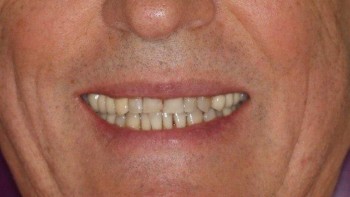

Ведерникова Елена Леонидовна принимает в «ЦЕНТР ГНАТОЛОГИИ ЕЛЕНЫ ВЕДЕРНИКОВОЙ» в Ростове-на-Дону. Главный врач, врач высшей категории, стаж 29 лет. Специализируется на ортодонтии и гнатологии, по которым клиника оказывает 4 услуги. Имеет 5 работ до/после в портфолио. Квалификация специалиста подтверждена 5 лицензиями, сертификатами и наградами. Для уточнения дополнительной информации о специалисте или записи на прием можно позвонить по телефону

5 работ в портфолио

Владеет всеми новейшими американскими технологиями создания голливудской улыбки. Совместно со специалистами Бостонского института проводит комплексное лечение по принципам нейромышечной и эстетической стоматологии, заболеваний височно-нижнечелюстного сустава.